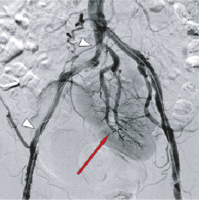

Abbildung 1: DSA-Beckenübersicht. Verschluss der A. iliaca communis rechts (roter Pfeil) und Demaskierung einer Nierenektopie mit verschlussnahem Abgang („upstream“) der Nierenarterie (weißer Pfeil), retrograde Perfusion der proximal verschlossenen A. iliaca interna (blauer Pfeil). Eine orthotope Niere kommt nicht zur Darstellung.